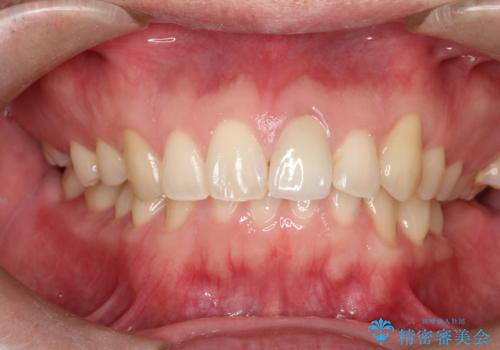

前歯が黒くなってきた。オールセラミッククラウン

- 前歯の変色を主訴に来院されました。

根管治療は希望されなかったので、リスクを説明した上でオールセラミッククラウンの治療を行っています。

金属の被せ物は歯肉の変色を起こしやすくなります。オールセラミッククラウンは金属を使わないため審美的な治療を行うことができます。